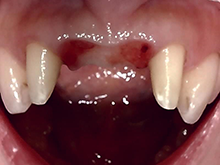

ハイブリッドセラミックス

ハイブリッドセラミックスとはセラミック粒子を92%含有した白い材料で、セラミックスのもつ審美性と耐久性、

より天然歯に近い硬さの材料です。

症 例